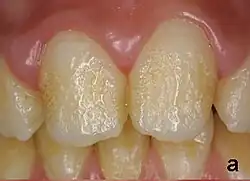

Pitting enamel hypoplasia

Enamel hypoplasia can take a variety of forms, but all types are associated with a reduction of enamel formation due to disruption in ameloblast production.[1] One of the most common types, pitting enamel hypoplasia (PEH), ranges from small circular pinpricks to larger irregular depressions.[2] Pits also vary in how they occur on a tooth surface, some forming rows and others more randomly scattered.[3] PEH can be associated with other types of hypoplasia, but it is often the only defect observed.[4] Causes of PEH can range from genetic conditions to environmental factors, and the frequency of occurrence varies substantially between populations and species, likely due to environmental, genetic and health differences. The most striking example of this is in Paranthropus robustus, with half of all primary molars, and a quarter of permanent molars, displaying PEH defects, thought to be caused by a specific genetic condition, amelogenesis imperfecta.[1]

Each pit is linked to the ceasing of ameloblasts at a particular point in enamel formation. Sometimes, only a couple of ameloblasts stop forming enamel, leading to small PEH defects, with large pits forming when hundreds of these enamel-forming cells stop production.[6] This does not occur in other forms of enamel hypoplasia, such as linear and plane-form, in which all ameloblast activity is affected.[4] Typically with PEH described in archaeological reports, researchers can not specify a cause, with a non-specific stress often concluded. However, in modern clinical studies it is often possible to suggest a cause and these can include the following conditions:[1]